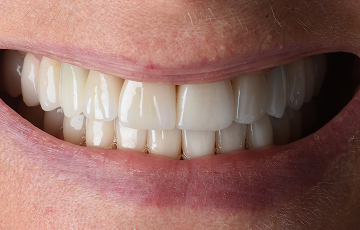

Mejora Estética

- Diseño de sonrisa natural armonizado con proporciones faciales.

- Restauración del soporte facial revirtiendo el envejecimiento por pérdida dental.

- Morfología dental personalizada, tonalidad y translucidez para estética natural.

Rehabilitacion Definitiva

Colocamos las restauraciones finales con enfoque estético y funcional, cuidando contactos, anatomía y transición con la encía para un resultado natural.